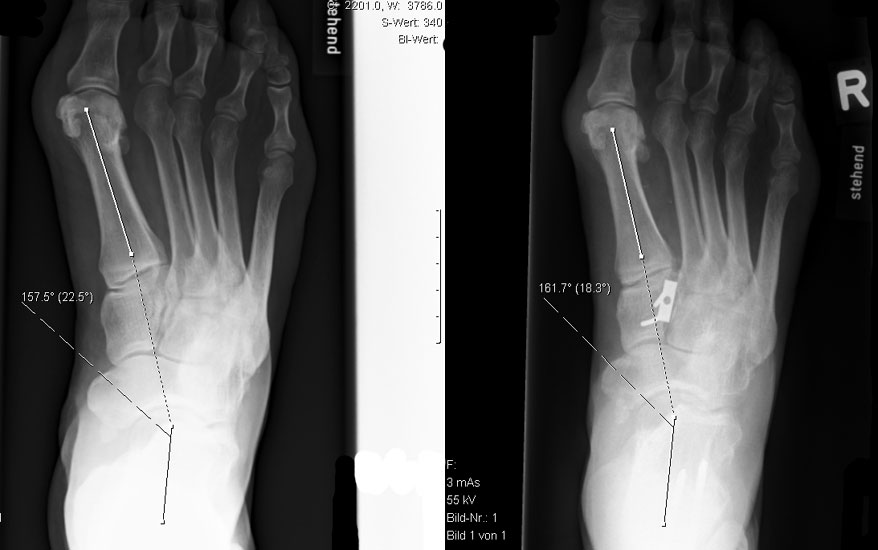

Dorsalflektierende Osteotomien des medialen Mittelfuβes (Abb. 6 – 9, Video 4)

• Erhöhter lateraler Talo-Metatarsale I Winkel (Meary-Winkel) als Ausdruck des plantarflektierten medialen Mittelfuβes, insbesondere im "forefoot driven hindfoot varus" (positiver Coleman block Test).

Die reduzierte Steilstellung des 1. Strahls wirkt sich positiv auf den Rückfuβ varus und den Vorfuβ adductus aus. Auch die relative Dorsalflexion des Talus in der Sprunggabel mit anterioren OSG-Impingement und verringerter OSG-Dorsalflexion wird verbessert.

Generell wird die dorsalflektierende MT I Osteotomie (Abb. 6 und 7) nicht isoliert ausgeführt, sondern ist Teil der gesamten Hohlfuβ-Korrektur. Beim absolut flexiblen Hohlfuβ ist sie gelegentlich zusammen mit einem Peroneus longus auf brevis oder einem Release der Plantarfaszie ausreichend. Diese Osteotomie ist einfach durchzuführen und hat eine geringe Pseudarthroserate.